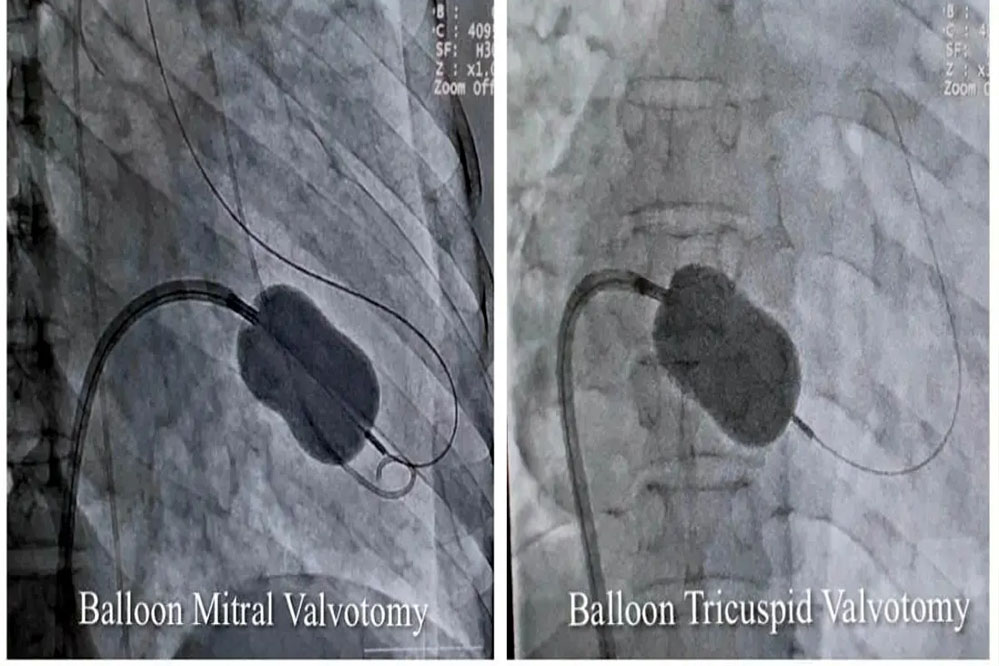

जबलपुर में विशेषज्ञों ने बैलून तकनीक से मिट्रल व ट्राइकसपिड वॉल्व की सिकुड़न का बिना सर्जरी के इलाज किया

रयूमेटिक हृदय रोग से पीड़ित 40 वर्षीय महिला का मेडिकल कॉलेज के सुपर स्पेशलिटी अस्पताल के विशेषज्ञों ने बैलून तकनीक से मिट्रल व ट्राइकसपिड वॉल्व की सिकुड़न का बिना सर्जरी के इलाज किया। उपचार से मरीज को धड़कन की अनियमितता, बीपी, फेफड़े, पेट व अन्य जगह पर पानी भरने में भी आराम मिला है।

कार्डियोलॉजी विभाग के हृदय रोग विशेषज्ञ और ऐसोसिएट प्रोफेसर डॉ. शिशिर सोनी ने बताया कि मरीज को अत्यधिक गम्भीर अवस्था में सुपर स्पेशलिटी अस्पताल लाया गया था। इससे पहले उसे महाकोशल के कई अस्पतालों और नागपुर के हृदय रोग विशेषज्ञों को दिखाया जा चुका था, लेकिन इलाज नहीं हो सका। डॉ. सोनी ने बताया कि मरीज के मिट्रल और ट्राइकसपिड दोनों वॉल्व में स्टेनोसिस (सिकुडऩ) थी। इस बीमारी में मरीज को अत्यधिक सांस फूलने और पैरों में सूजन की समस्या होती है। इसके अलावा अन्य समस्याएं धडकऩों की अनियमितता, कम बीपी और फेफडें, पेट और अन्य जगहों में पानी भर जाने जैसी परेशानियां भी थीं। उन्होंने बैलून तकनीक से एक ही बार में परक्यूटेनियस मिट्रल और ट्राइकसपिड बैलून वाल्यूलोप्लास्टी सफलतापूर्वक की। इलाज के बाद महिला को पूर्णत: लाभ मिला है।

डॉ. शिशिर सोनी ने बताया कि एक ही मरीज में दोनों वॉल्व की सिकुड़न का परक्यूटेनियस मिट्रल और ट्राइकसपिड बैलून पाल्यूलोप्लास्टी से सफलतम उपचार दुनिया के कुछ ही कार्डियेक सेंटर में हुआ है। मध्यप्रदेश में यह उपचार पहली बार किया गया है।